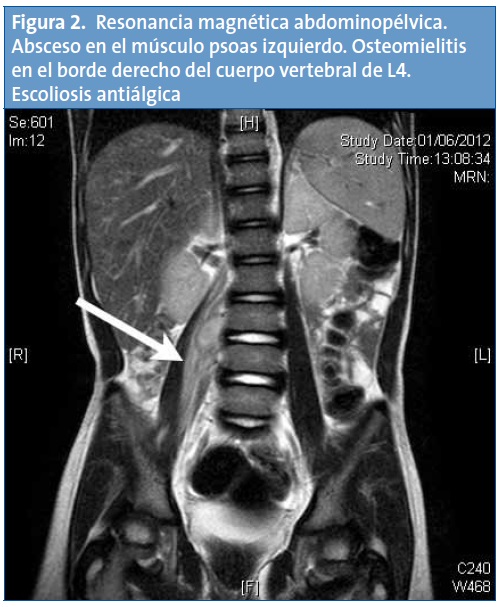

Ingresó con tratamiento con amoxicilina-clavulánico por vía intravenosa. Dada la normalidad de las pruebas realizadas y ante la sospecha clínica de absceso de psoas se solicitó una resonancia magnética (RM) abdominal que mostró un absceso en el músculo psoas derecho y una osteomielitis del cuerpo vertebral L4 (Fig. 2). El hemocultivo fue estéril, pero en la punción del absceso del cuero cabelludo se aisló Staphylococcus aureus resistente a meticilina, por lo que se modificó la antibioterapia para cubrir dicho germen, con meropenem y linezolid. El paciente evolucionó favorablemente, sin que fuera necesario drenaje quirúrgico.